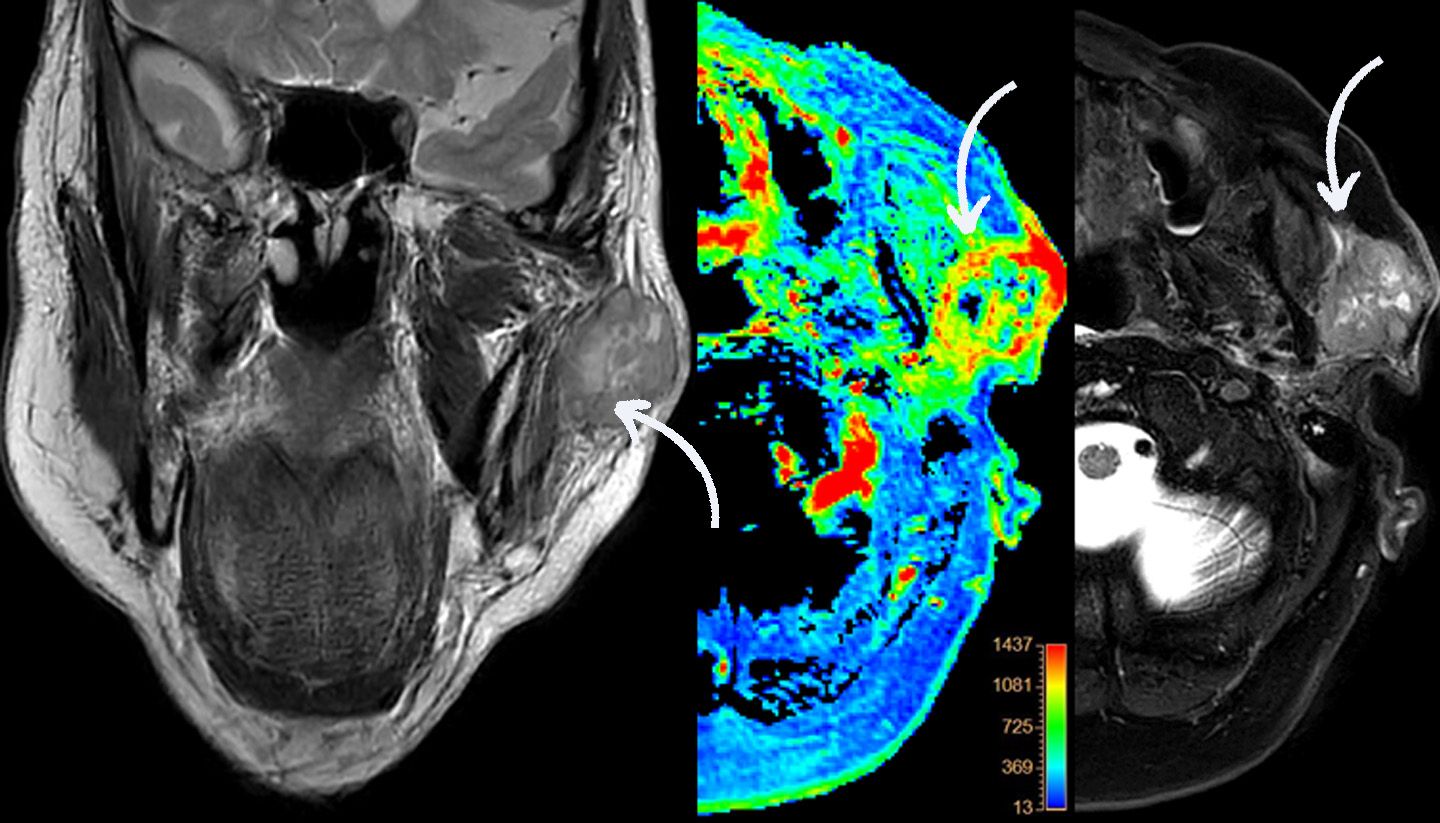

Detaillierte MRT-Untersuchung zur Darstellung eines Tumors in der Ohrspeicheldrüse (Parotisdrüse).

MRT (Magnetresonanztomographie)

Ohne Strahlung werden mit Hilfe eines starken Magnetfeldes detaillierte Bilder (sogenannte Sequenzen) von Gehirn, Rückenmark, Nerven, Weichteilen und Knochen erstellt.